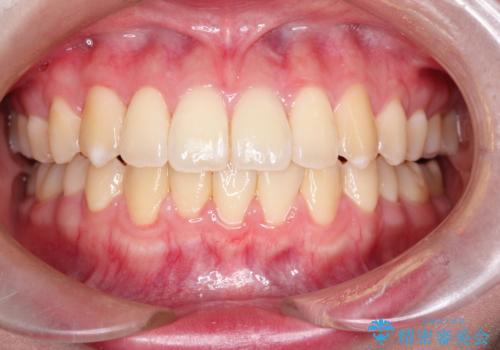

【インビザライン】前歯を下げたい。

- 前歯が出ていることを主訴に来院されました。

下顎前歯が1本欠損していることもあり、前突はある程度残ることを説明し、インビザラインにて治療を行いました。

今回は抜歯矯正ではなく歯列弓の拡大とIPR、遠心移動を行って配列することができました。

口元も改善し患者さんには喜んでいただけました。

下顎前歯が1本少ないため、上下の正中は合いません。